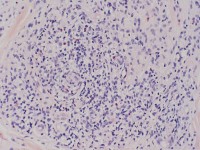

hypereosinofiele dermatitis hypereosinofiele dermatitis